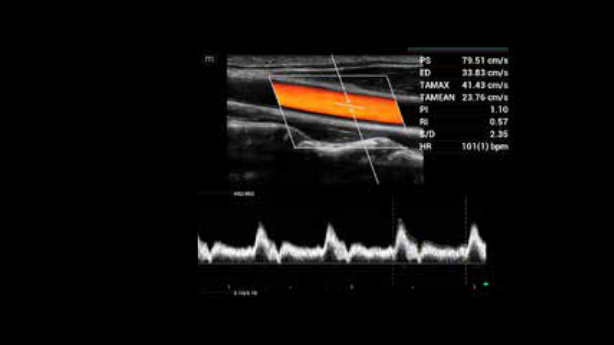

System ultrasonograficzny Zeus jest wyposa?ony w?przyjazny interfejs u?ytkownika i??atwe w?u?yciu funkcje umo?liwiaj?ce skuteczne skanowanie. Jego wszechstronne funkcje obejmuj? ultrasonografi? jamy brzusznej, naczyniow?, ma?ych narz?d├│w i?uk?adu mi??niowo-szkieletowego, zwi?kszaj?c pewno?? diagnostyczn?.